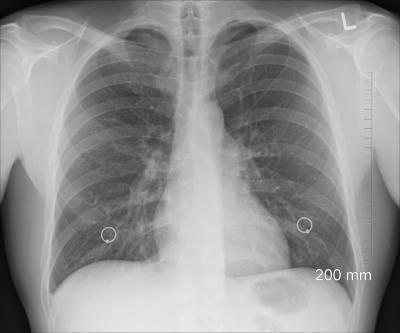

सॉफ्टवेअर कोड व्यक्तीची छाती स्कॅन करून शरीरात लपून बसलेल्या कोरोनाचा शोध घेऊ शकतं असा दावा नारायणन यांनी केला आहे.

कोरोनासाठी तयार करण्यात आलेले हे खास सॉफ्टवेअर सामान्य एक्स रे स्कॅनिंग मशीनपेक्षा एकदम वेगळं आहे. आर्टिफिशिल इंटेलिजन्सच्या मदतीनेच तयार करण्यात आले आहे.

नारायणन गेल्या अनेक दिवसांपासून आर्टिफिशिल इंटेलिजन्स तंत्रज्ञानावर काम करत आहेत. कारण त्याच्या मदतीने डॉक्टर लवकर रुग्णांचा आजार ओळखून योग्य ते उपचार करू शकतात.